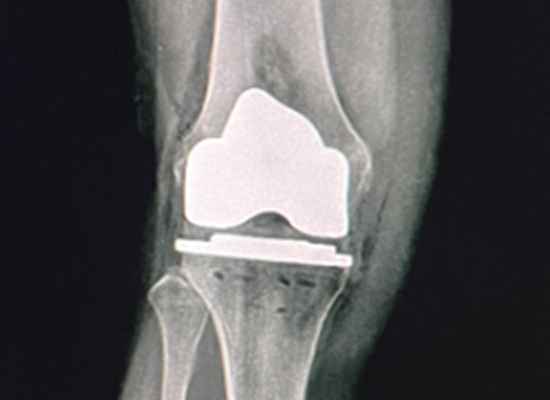

Postoperative Imaging

Postoperative X-ray - Anterior View